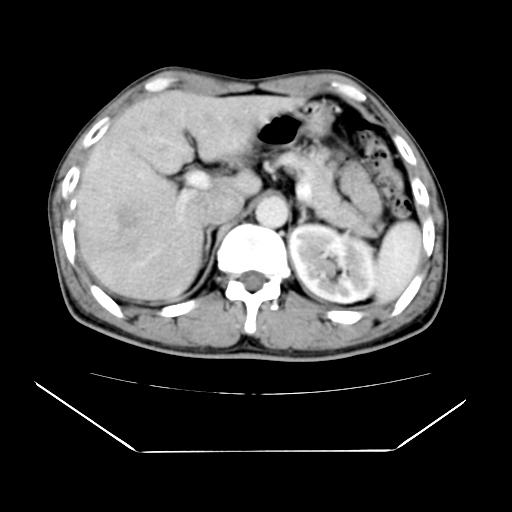

男性,55岁,外院体检afp明显升高,但b超未发现异常,否认乙肝病史。来我院ct增强。有延时扫描。

延时扫描完全充填,血管瘤

肝脏右叶动脉期可见低密度影,至延迟期被充填,考虑血管瘤可能性大。

不排除肝右叶肝癌可能。

如果这个是癌灶的话则下腔静脉有瘤栓可能

肝6段血管瘤

血管瘤可能性大。

考虑肝右静脉影。